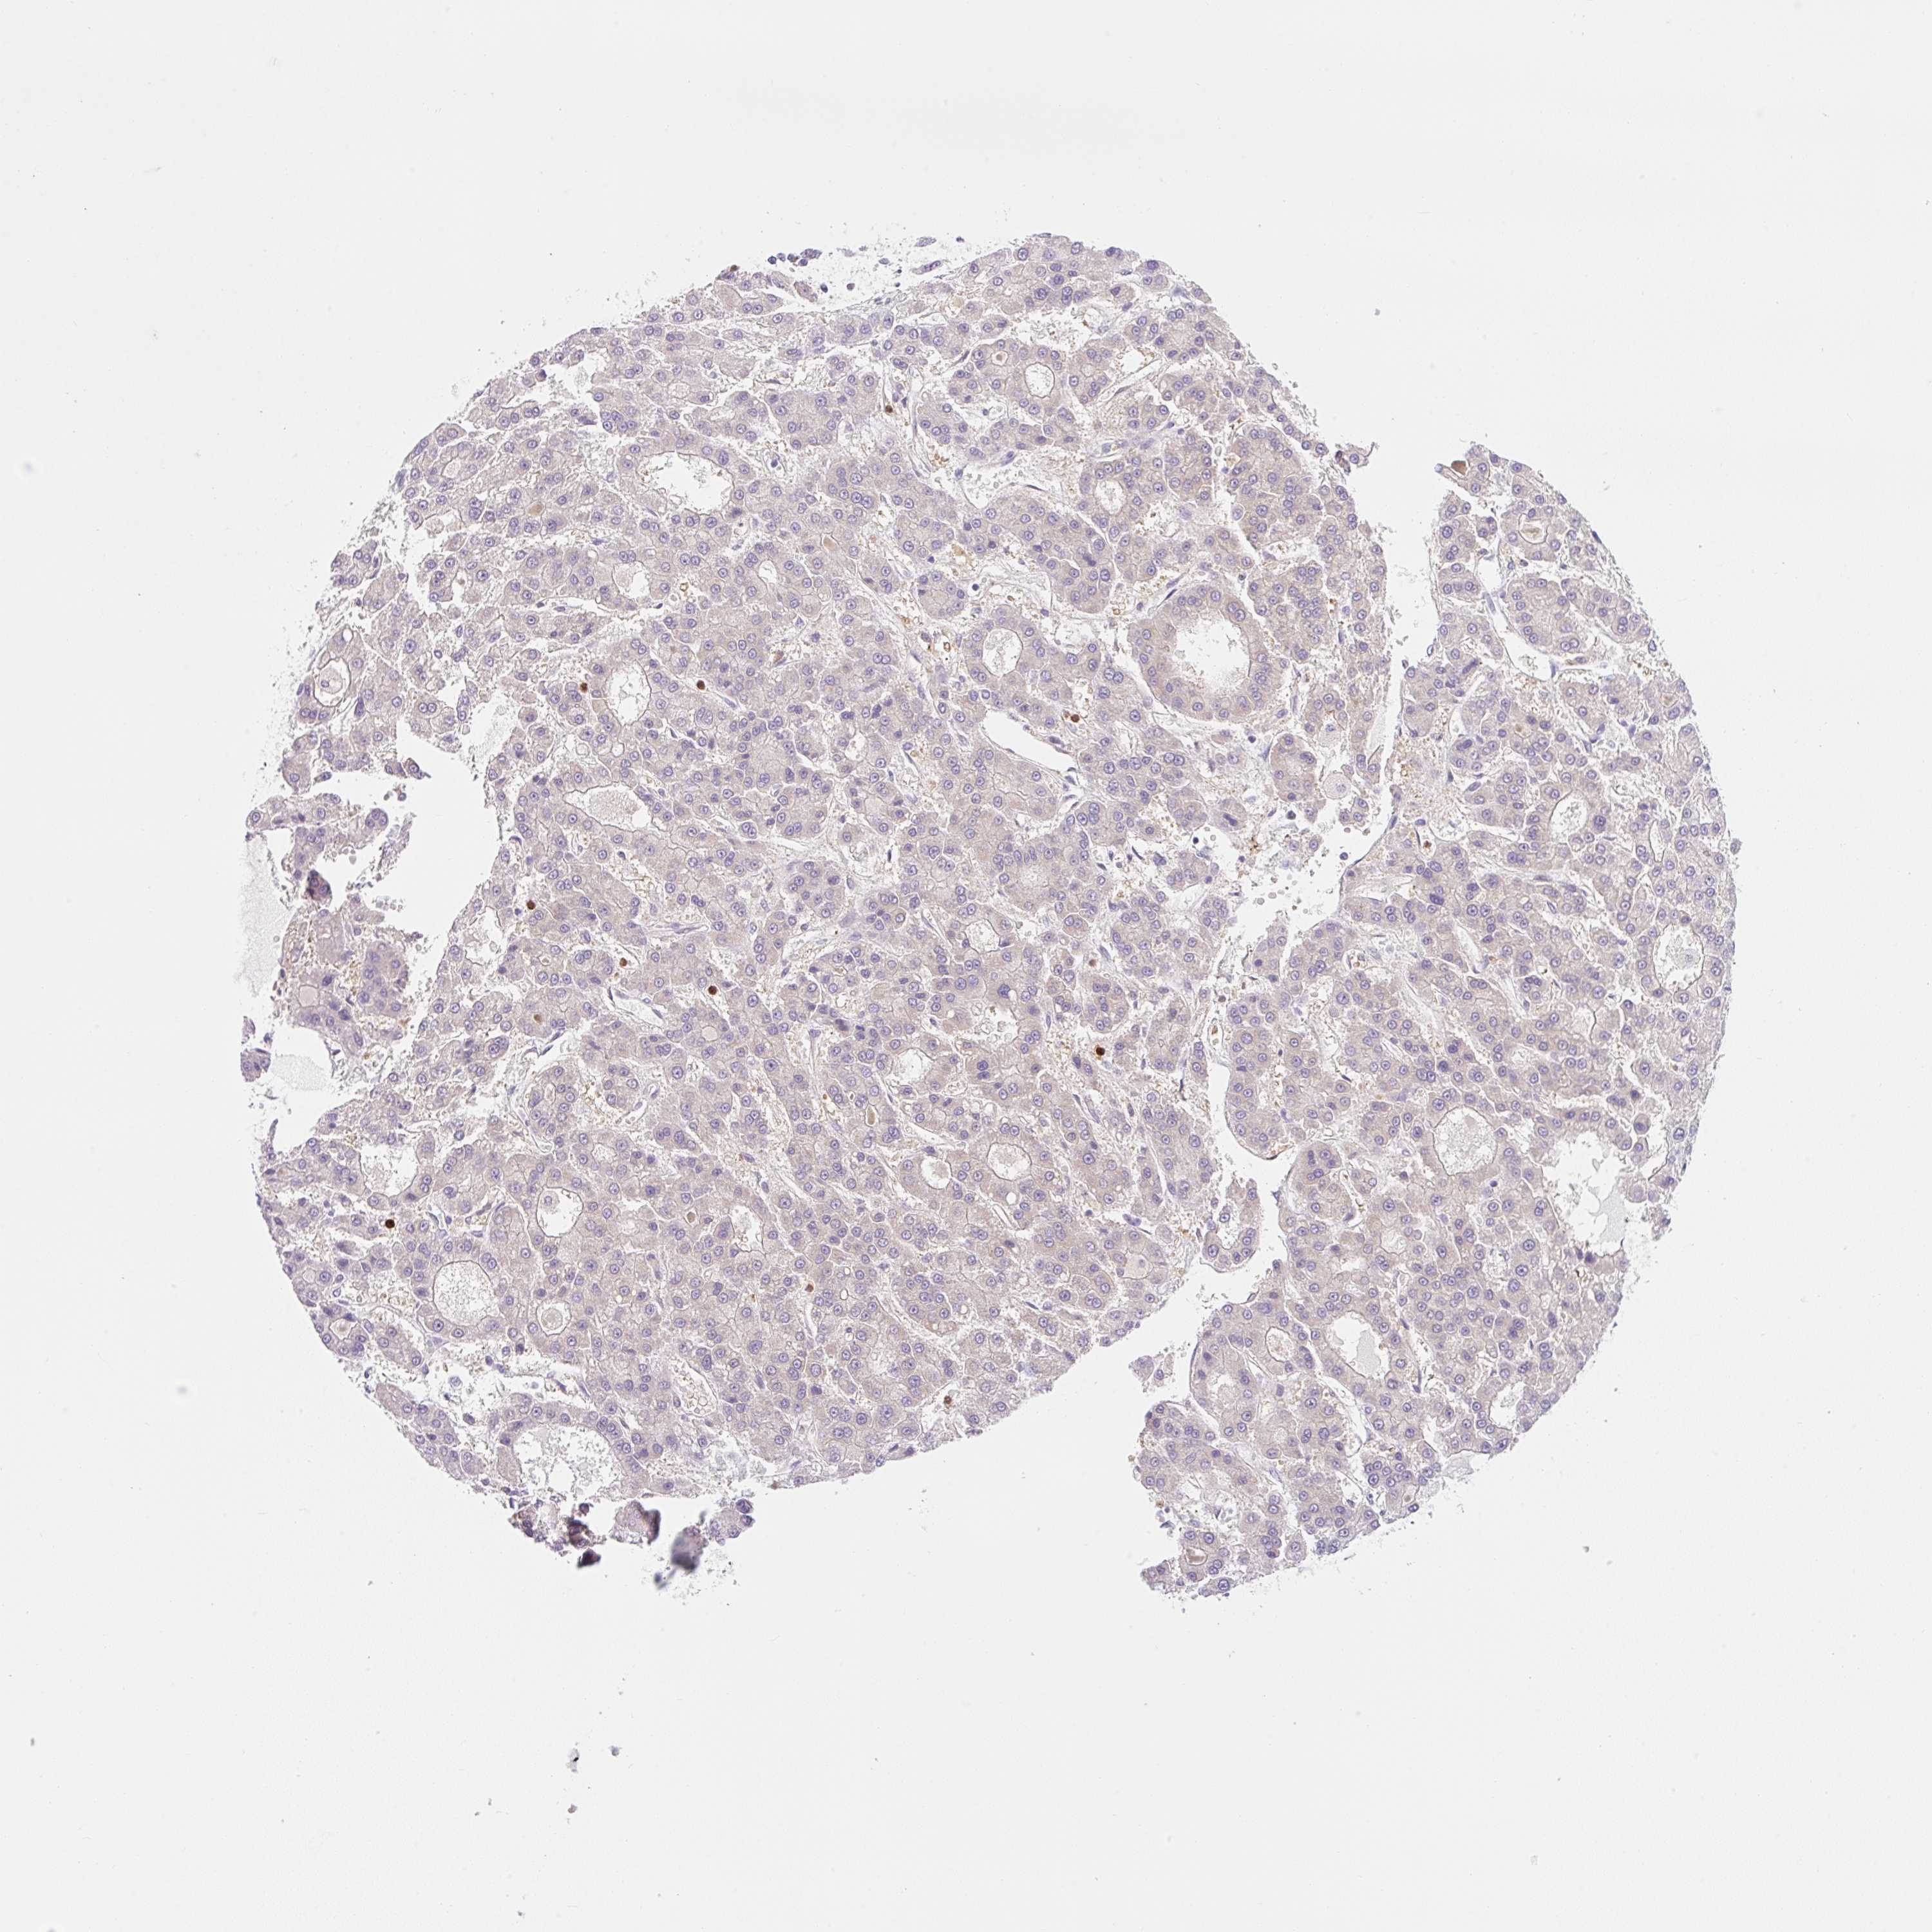

LIVER CANCER - Protein expressioni

A mouse-over function shows sample information and annotation data. Click on an image to view it in a full screen mode. Samples can be filtered based on level of antibody staining by selecting one or several of the following categories: high, medium, low and not detected. The assay and annotation is described here.

Note that samples used for immunohistochemistry by the Human Protein Atlas do not correspond to samples in the TCGA dataset.

Antibody stainingi

Antibody staining in the annotated cell types in the current human tissue is reported as not detected, low, medium, or high, based on conventional immunohistochemistry profiling in selected tissues. This score is based on the combination of the staining intensity and fraction of stained cells.

Each image is clickable and will lead to virtual microscopy that enables deeper exploration of all samples and also displays staining intensity scores, fraction scores and subcellular localization as well as patient and tissue information for each sample.

Antibody HPA055120

Staining

High

Medium

Low

Not detected

Intensity

Strong

Moderate

Weak

Negative

Quantity

>75%

75%-25%

<25%

None

Location

Nuclear

Cytoplasmic/membranous

Cytoplasmic/membranous,nuclear

Cholangiocarcinoma

Carcinoma, Hepatocellular, NOS